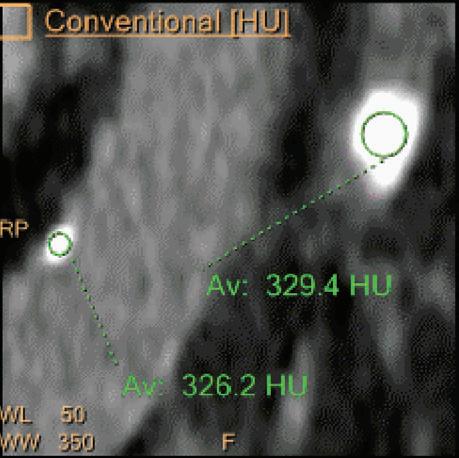

Uric Acid [HU]

Voxels which are classified as including uric acid show the corresponding HU of the reference monoenergetic 70 keV CT image. Other voxels appear black. This image is useful to identify uric acid stones and separate them from calcified stones (Figure 6).

Double oblique MPR image shows a calcified lesion and a uric acid stone side by side. The lower row displays spectral results in the Magic Glass, from left to right: conventional CT image, uric acid removed image, uric acid image, and Z effective map image. A comparative measurement on the conventional image shows that it is not possible to differentiate between them based on HU measurements (Calcified: 326.2 HU; UA stone: 329.4 HU). The Z effective map shows a large difference between the lesions (Calcified: 10.0; UA stone: 7.0) which enables us to classify them correctly.